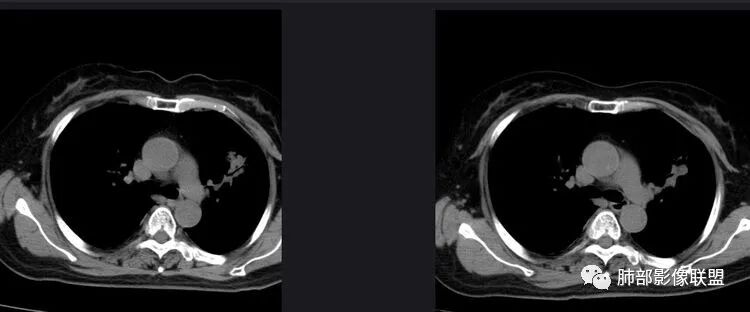

以下是两个时间点左右对比

2019.11.26  👇                           2020.01.20👇                                            2019.11.26片

2020.01.20片

3.复查影像显示病灶整体大小变化不明显,其内空泡消失,但是周围磨玻璃影趋于似清非清,整体病灶收缩力中等偏弱,均提示粘液腺癌的可能性大。